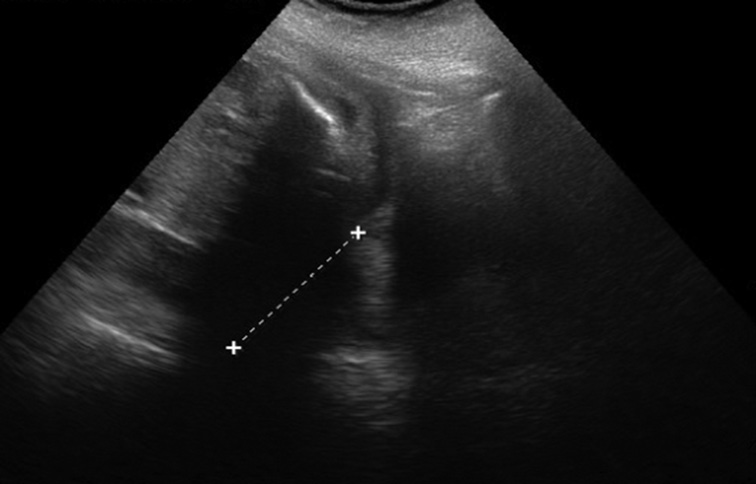

Измерение соотношения ширины нижней челюсти и ширины верхней челюсти производилось в осевом положении на уровне альвеолярного отростка 10 мм кзади от передней костной границы (рис. 5, 6). Среднее значение этого коэффициента равно 1,02 ± 0,12 (SD), следовательно, коэффициент меньше 0,78.

Рис. 5. Длина нижней челюсти / Fig. 5. Length of the lower jaw

Оценка развития челюстей также оценивалась по длине нижней челюсти — длина нижней челюсти в соотношении с биометрией плода (длиной бедренной кости). При измерении длины нижней челюсти проксимальным ориентиром становился височно-нижнечелюстной сустав. Увеличение длины нижней челюсти соотносится с увеличением срока гестации от 20 мм в 20 недель до 37 мм в 28 недель.

Челюстной индекс рассчитывался после измерения переднезаднего диаметра нижней челюсти плода в осевой плоскости в соотношении с бипариетальным размером (рис. 7). Данный индекс не зависел от срока гестации.